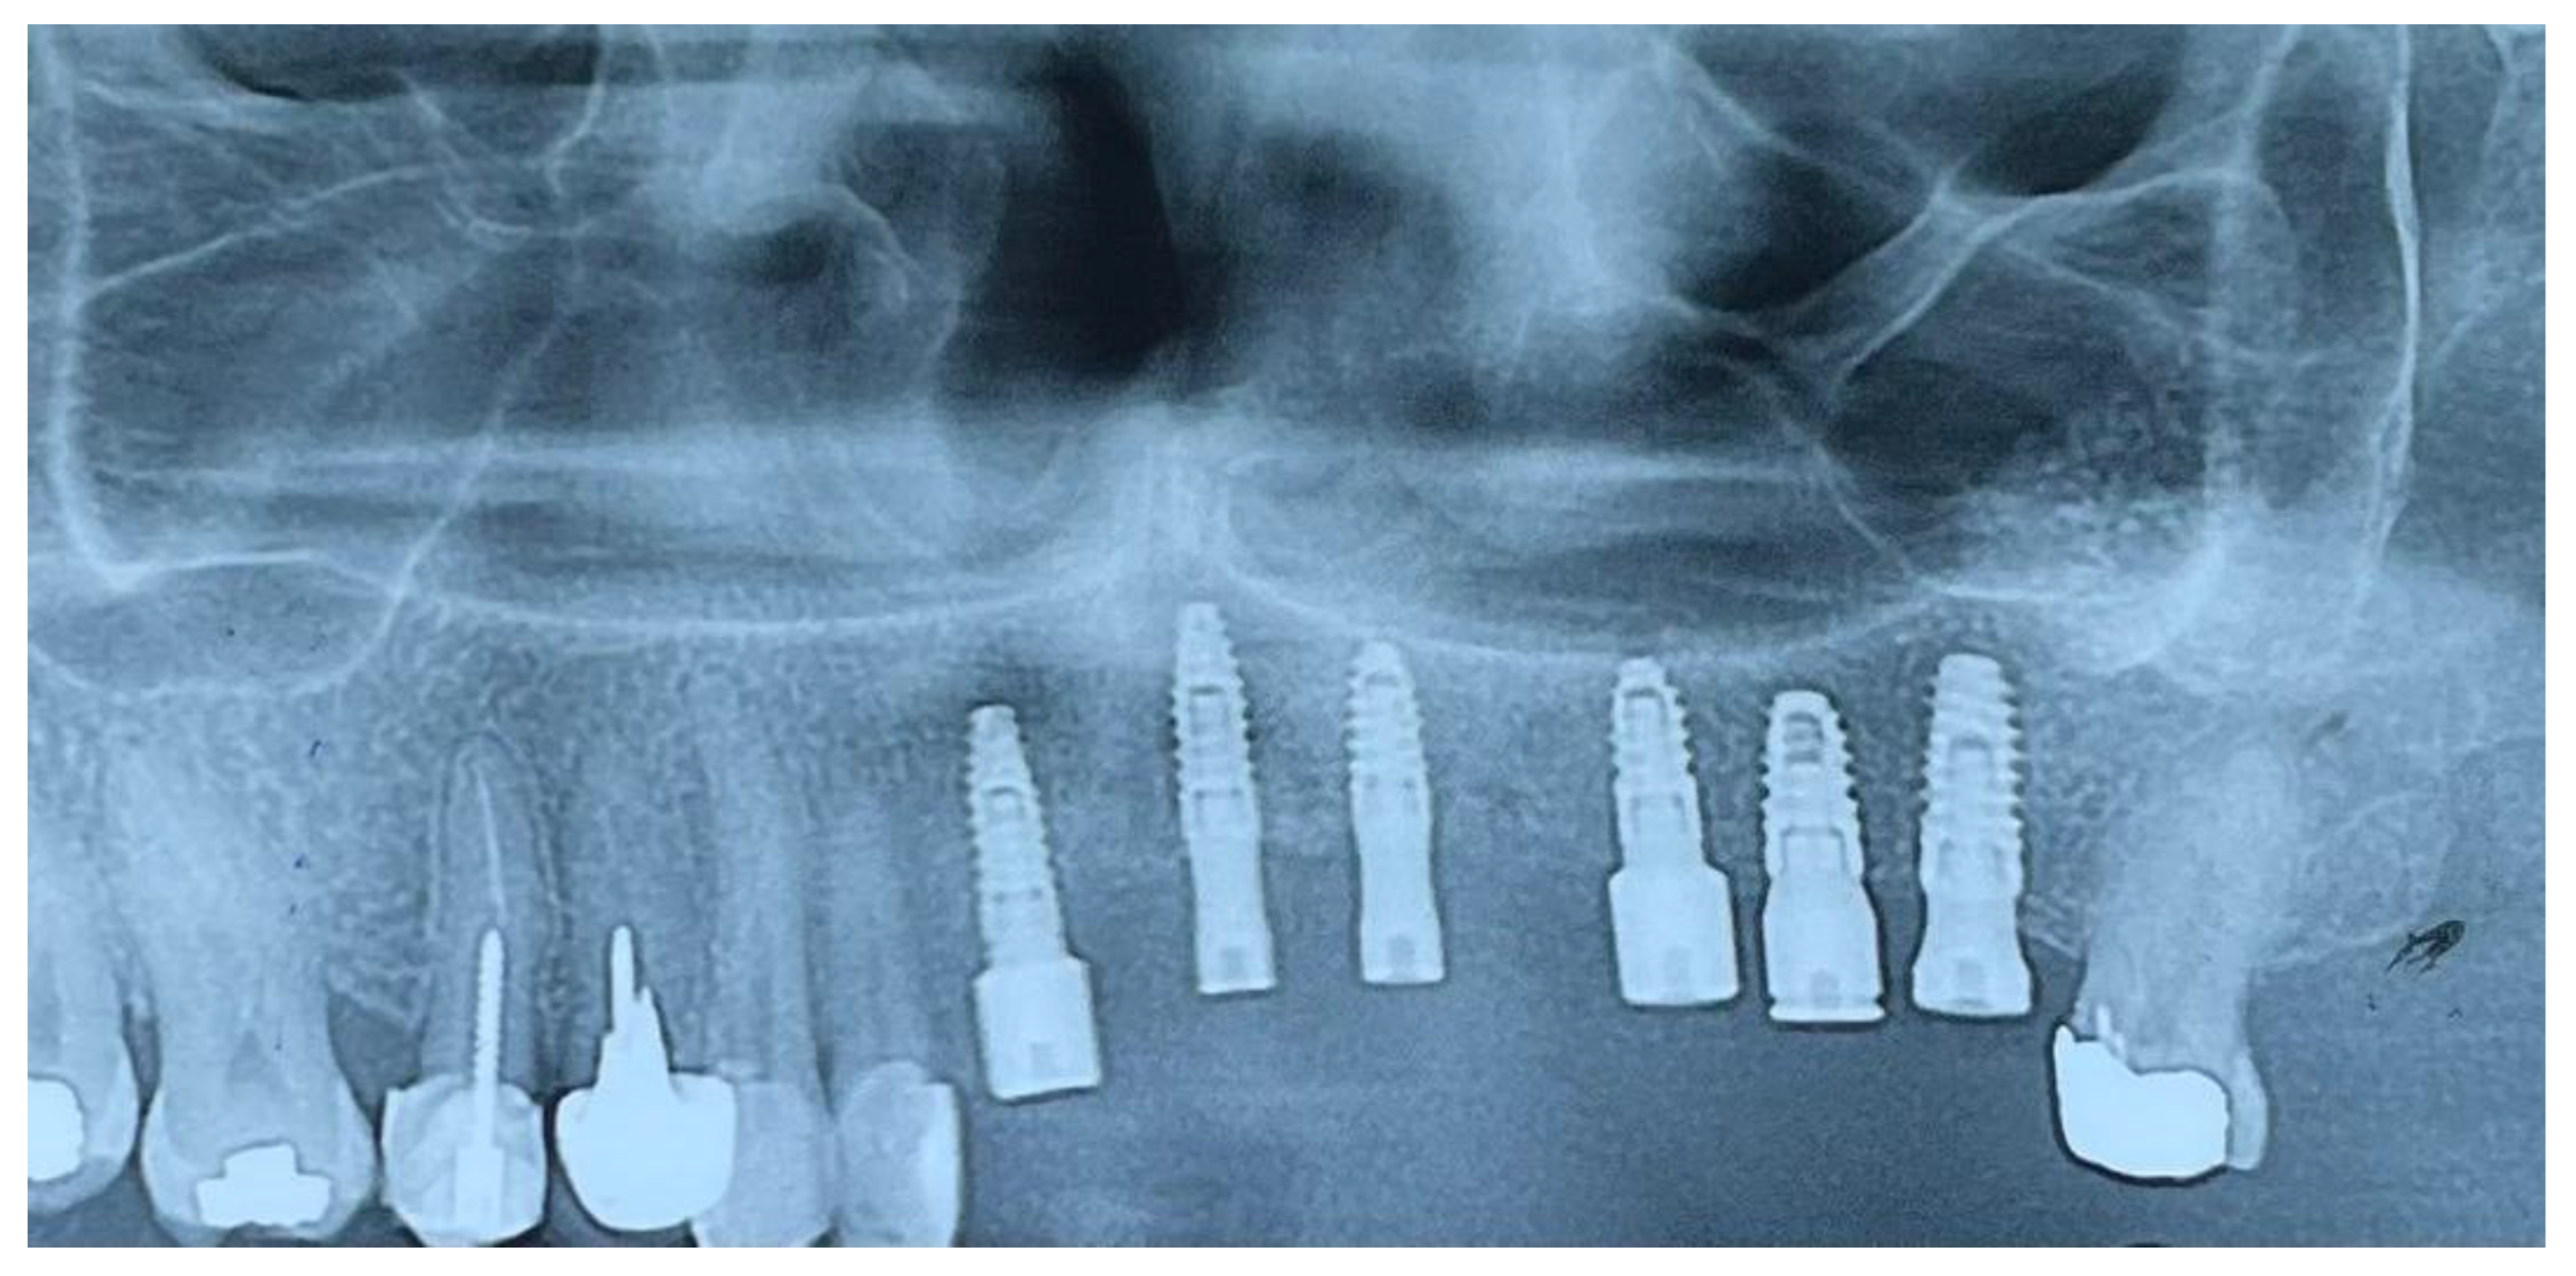

At six months post-augmentation, CBCT evaluation confirmed sufficient bone volume and density to proceed with implant placement. Six IRES Swiss implants were inserted according to the prosthetic plan: two 3.3 × 10 mm fixtures in the maxillary central incisor positions (teeth #1), one 3.3 × 8 mm fixture in the lateral incisor site (tooth #2), one 3.3 × 8 mm fixture in the first premolar site (tooth #4), one 3.7 × 8 mm fixture in the second premolar site (tooth #5), and one 3.7 × 10 mm fixture in the first molar site (tooth #6). Primary stability was achieved in all sites. The postoperative panoramic radiograph confirmed accurate three-dimensional implant positioning, parallelism, and intimate bone contact along the implant surfaces. The surgical procedure began with a crestal alveolar incision to expose the augmented ridge. Sequential osteotomy preparation and placement of IRES Swiss dental implants were performed according to the planned positions. Following implant placement, cortical cancellous allograft was applied around the implants to increase alveolar ridge width, which not only enhanced bone thickness but also improved labial support (Figure 8) .

CBCT scans at follow-up confirmed stable bone levels and healthy peri-implant soft tissue with no measurable bone loss(Figure 9).

Figure 8. Surgical stages of implant placement: (A) crestal alveolar incision; (B, C) sequential placement of IRES Swiss dental implants at planned sites; (D) application of cortical cancellous allograft around implants to increase alveolar ridge width and enhance labial support.

Figure 9. CBCT scan taken six months after implant placement showing stable bone levels around all implants with no detectable bone loss (0 mm).